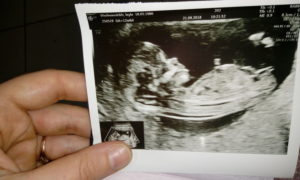

Если женщина не проводила ультразвуковое исследование плода на более ранних сроках, то УЗИ на 12 неделе беременности становится первым и приобретает особое значение.

Срок уже позволяет маме разглядеть малыша целиком, пусть пока и на мониторе оборудования. А доктор имеет возможность оценить анатомические особенности плода и рассказать о них будущей матери.

С медицинской точки зрения, УЗИ-скрининг 12 недель (1 триместра) представляет немалую ценность для определения мероприятий по дальнейшему ведению беременности и сохранению здоровья малыша.

К 12 неделям беременности все органы ребёнка и системы его организма полностью сформированы.

Справка! Вес малыша сейчас – не больше 19 граммов, а длина тельца – около 9 см.

Несмотря на крошечные параметры, головной мозг ребёнка уже ничем, кроме размера, не отличается от мозга взрослого человека.

Нередко на УЗИ женщина видит, как малыш сосёт пальчик, причём его ноготки уже сформированы. Хаотичные движения крохи продуманы природой – во время них он тренирует свой мышечный аппарат.

Что же такое УЗИ на 12 неделе беременности с точки зрения информативности, и что смотрят с его помощью? УЗИ-скрининг в 12 недель гестации позволяет врачу увидеть и оценить:

• размеры будущего младенца (фиксируется длина определённых костей, длина тела и параметры головки);

• симметричность полушарий мозга;

• местонахождение почек, желудка, сердца и других важнейших органов;

• возможные отклонения в развитии, среди которых пороки сердца, опухоли, врождённые аномалии;

• признаки генетических нарушений;

• место закрепления плаценты (в норме она должна быть расположена по передней или задней стенкам матки);

• состояние пуповины, наличие и функционирование в ней 2 артерий и вены;

• длину шейки матки, которая зависит от срока беременности и индивидуальных особенностей будущей мамы;

• точный срок от зачатия ребёнка.